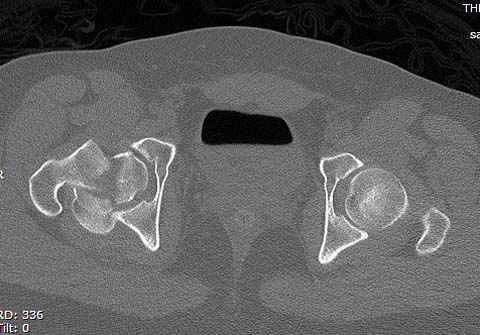

КТ после вправления - это последнее?

На мой взгляд, развитие артроза и AVN в большей степени зависит от давности вывиха и качества оперативной техники. Хирургический вывих бедра- не самая простая процедура и с подводными камнями, в остеосинтезе из переднего доступа тоже есть проблемы.

Здесь значимый задний край с подвывихом бедра кзади и острым краем вертлуги - задний доступ с вывихом и синтезом заднего края винтами и пластиной

Здесь клинические примеры: Первый случай передний доступ, второй с ICP monitor Flipp Trochanteris

и с переломом заднего края.